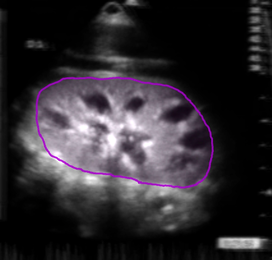

![[Kidney]](https://images.squarespace-cdn.com/content/v1/68926c61b505126b7e78f27f/f112e8dd-f483-4bb9-92ac-8c6ee2a92585/kidney-for-web.png)

[Kidney]